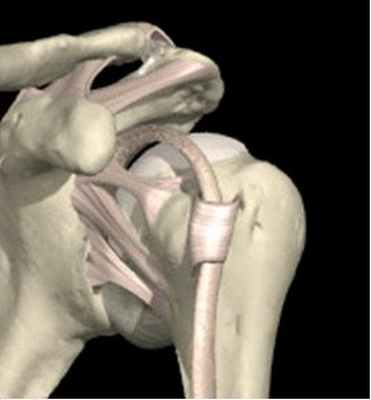

Механизмом травмы является чрезмерная наружная ротация отведенного плеча. Почему отведенного? Потому, что смещению головки приведенной плечевой кости за границы суставной впадины лопатки мешает клювовидный отросток. В результате же отведения больший сегмент головки плечевой кости находится ниже уровня клювовидного отростка. Под действием смещающего усилия возникает повреждение передних стабилизирующих структур капсулы (чаще всего отрыв суставной губы от надкостницы суставной впадины лопатки).

Рис. 3 Механизм отрыва суставной губы (правый плечевой сустав, вид спереди)

При продолжении действия смещающего усилия задняя часть головки плечевой кости перескакивает через передний край суставной впадины лопатки, что часто сопровождается образованием вмятины (импакционным переломом) на ее задней поверхности (так называемый дефект Хилл-Сакса). Возникает полное разобщение суставных поверхностей с заклиниванием головки плеча на переднем крае суставной впадины лопатки - передний вывих плеча (рис. 4). Если головка плечевой кости оказывается прочнее, происходит перелом суставной впадины лопатки, однако повреждение костей, составляющих плечевой сустав при переднем вывихе происходит в подавляющем большинстве случаев.

Рис. 4. Передний вывих плеча